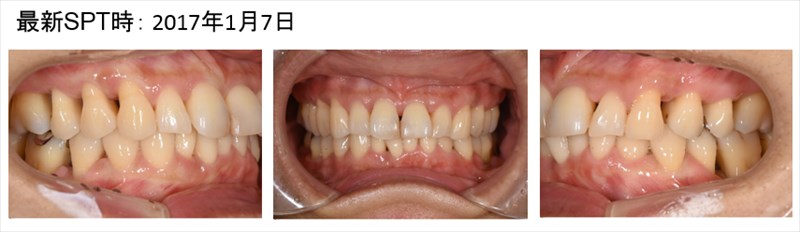

この症例は重症の歯周病の患者さまを1本たりとも歯を抜かず安定している症例です。

歯茎が腫れあがり膿をもっていました。青丸の部分です。全顎的に重度歯周病です。

骨が平坦になり歯ブラシのしやすい形態になって今年も安定しています。術後4年、問題なく1本も歯を失っていません。

術前の腫れは全く見られません。